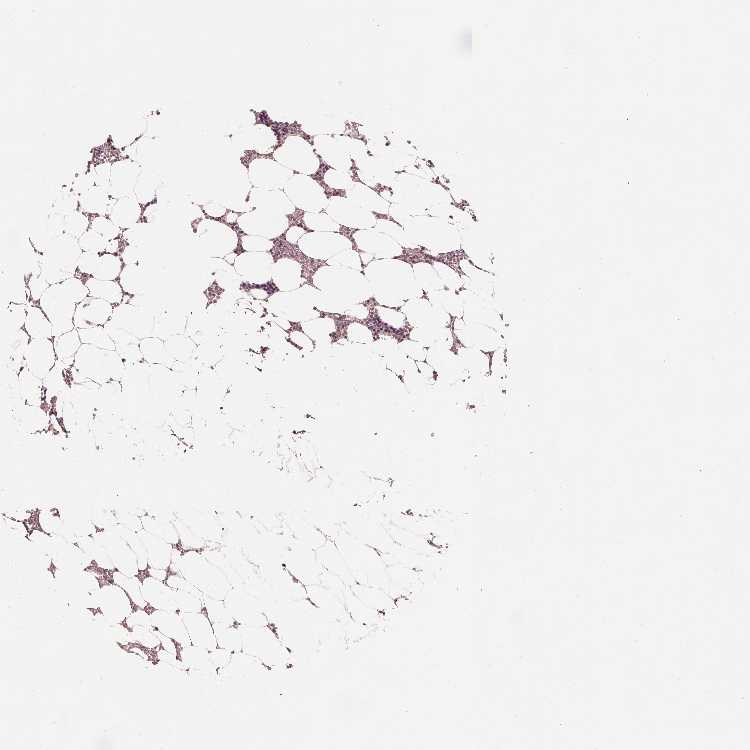

SNX12